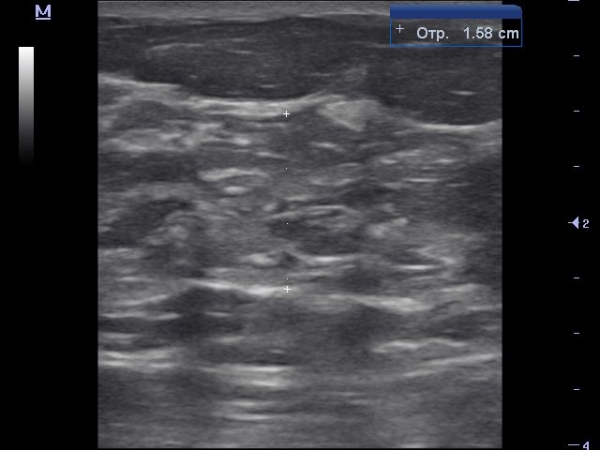

Темерь покажу какая должна быть структура железы в постменопаузальном периоде в норме, кстати кинопетля снята у этой же женщины с участка в нижне-внутреннем квадранте.

Вот пример когда паренхима железы полностью замещена жировой и фиброзной тканью, что характерно для постменопаузального типа строения молочной железы.